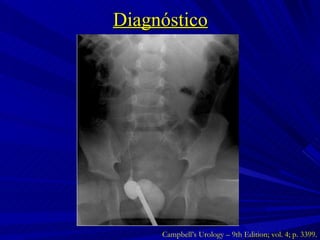

Diagnóstico Campbell’s Urology – 9th Edition; vol. 4; p. 3399.

Diagnóstico Campbell’s Urology – 9th Edition; vol. 4; p. 3402.